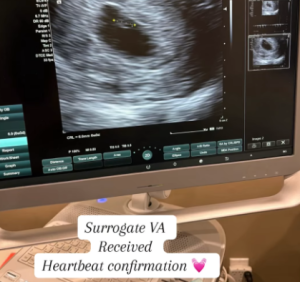

The Moment That Changes Everything

Babytree Surrogacy shares that Surrogate VA’s ultrasound confirms a healthy heartbeat, shown by a heart emoji on screen. babytree

Hearing the Heartbeat: The Milestone That Makes It Real

A Sound That Echoes Forever

There is a moment in every surrogate pregnancy that transforms hope into certainty: hearing the baby’s heartbeat for the first time.

For Surrogate VA, that moment came during a routine ultrasound appointment. The steady, rhythmic sound of a tiny heart beating strong filled the room — and filled her intended parents with a joy that words cannot capture.

VA later described it as “the moment everything became real.” Until then, the pregnancy existed as numbers on a test and dates on a calendar. But that heartbeat? That was a life. That was their child.

This milestone typically occurs around the 6-8 week mark and is one of the most emotional moments in the surrogacy timeline. Our month-by-month surrogacy timeline guide helps intended parents understand when each milestone typically occurs.